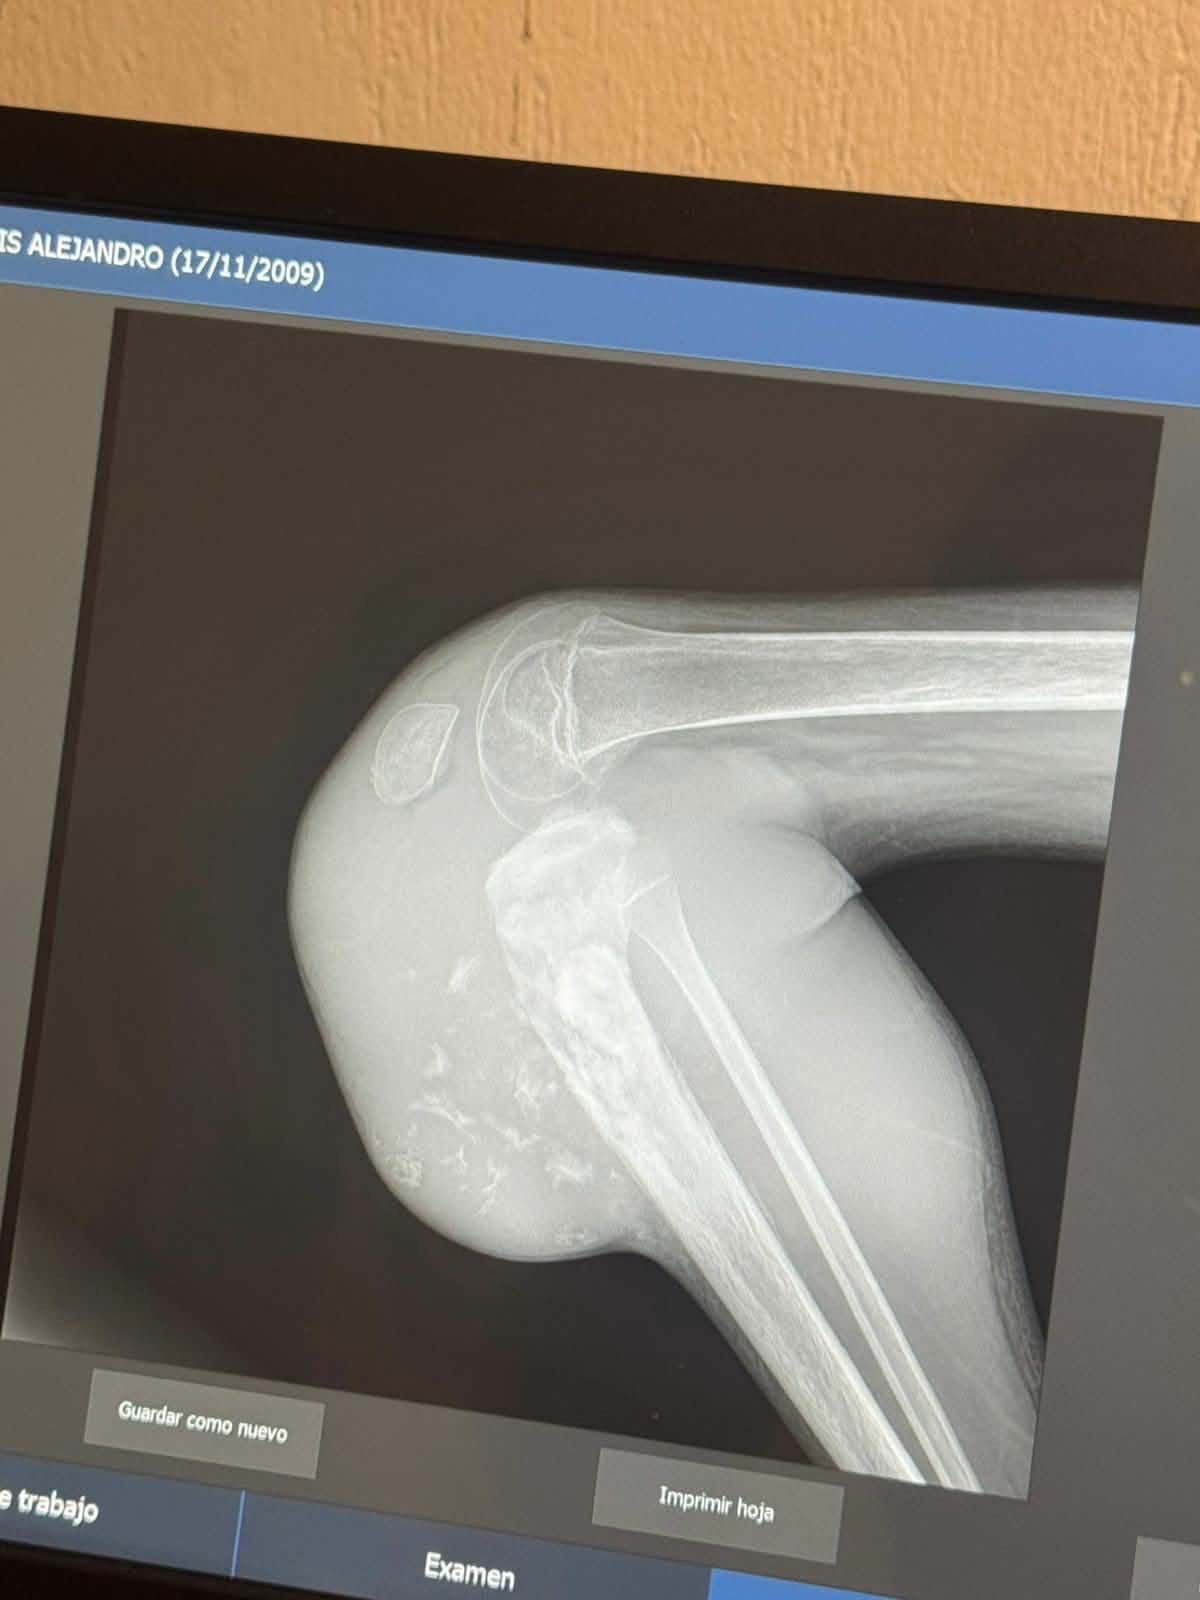

Luis is my best friend, and right now he’s facing one of the hardest challenges of his life. After being deported, he’s in Mexico and recently found out he has a large, infected tumor on his right knee. The doctors there have told him that the infection is so severe, they need to remove his leg. It’s a devastating situation, and being far from home makes it even harder for him to get the care he needs.